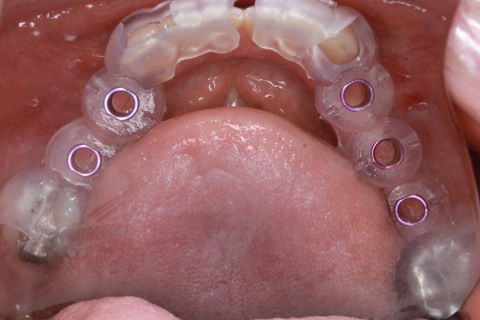

Guia em posição

Cicatrizadores em posição